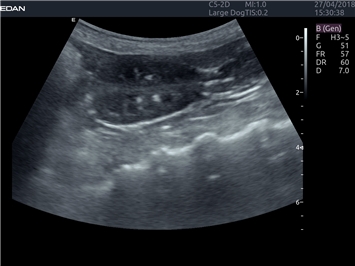

EDAN Acclarix LX4 VET

EDAN Acclarix LX4 VET представляет собой профессиональную ультразвуковую систему, специально разработанную для ветеринарных исследований. Сочетание стабильности, высокой производительности и эффективности делает эту систему идеальным выбором для современной ветеринарной практики.

• Универсальные датчики для различных видов животных

• Специализированные предустановки для ветеринарных исследований

Области применения:

Система оптимально подходит для:

• Ветеринарных клиник

• Специализированных ветеринарных центров

• Животноводческих комплексов

• Конных клиник

• Научно-исследовательских ветеринарных учреждений